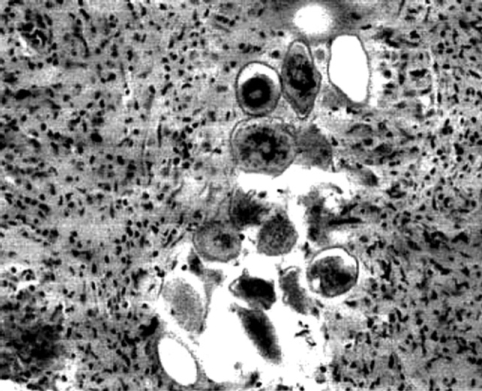

The herdsman was treated with antibiotics for 14 days as the tendentious diagnosis of atypical brain abscess, but still complained of dizziness and aggravating headache. Then a high-grade glioma was suspected, and an operation of total resection was performed to solve the mass effect and intracranial hypertension. However, the examination of a frozen section of the biopsy tissue specimen suggested S. japonicum ova and granulomas (Fig. 2). Pathologic examination of the biopsy specimen revealed sclerosing schistosomal granulomas scattered within the parenchyma of the cerebellum. The diagnosis was confirmed, and the patient was treated with praziquantel at the dose of 20 mg/kg per day for 6 days, with concurrent administration of dexamethasone. The patient was discharged after 24 days and he was followed up 3 months later with complete resolution of the symptoms. However, the patient was lost to follow-up after a period of 6 months.